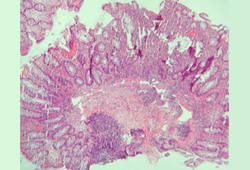

Deben obtenerse biopsias colónicas e ileales segmentarias para evaluar la evidencia microscópica de enfermedad de Crohn (EC).[70] Las características microscópicas que ayudan a distinguir la colitis ulcerosa y la EC son los granulomas, los cambios arquitectónicos y la distribución de la enfermedad.[81] Sin embargo, la inflamación granulomatosa se registra en una minoría de pacientes con EC (del 30% al 50%); no es necesaria para el diagnóstico.[71][81][Figure caption and citation for the preceding image starts]: Inflamación significativa de la pared del colon, engrosamiento de la submucosa y acumulaciones linfoides densas en la submucosaProporcionado por los doctores Wissam Bleibel, Bishal Mainali, Chandrashekhar Thukral, y Mark A. Peppercorn, los anteriores autores de este tema [Citation ends].

[Figure caption and citation for the preceding image starts]: Criptitis y abscesos de criptas con distorsión morfológica de las criptas acompañada de inflamación y abundantes células plasmáticas y linfáticasProporcionado por los doctores Wissam Bleibel, Bishal Mainali, Chandrashekhar Thukral, y Mark A. Peppercorn, los anteriores autores de este tema [Citation ends].